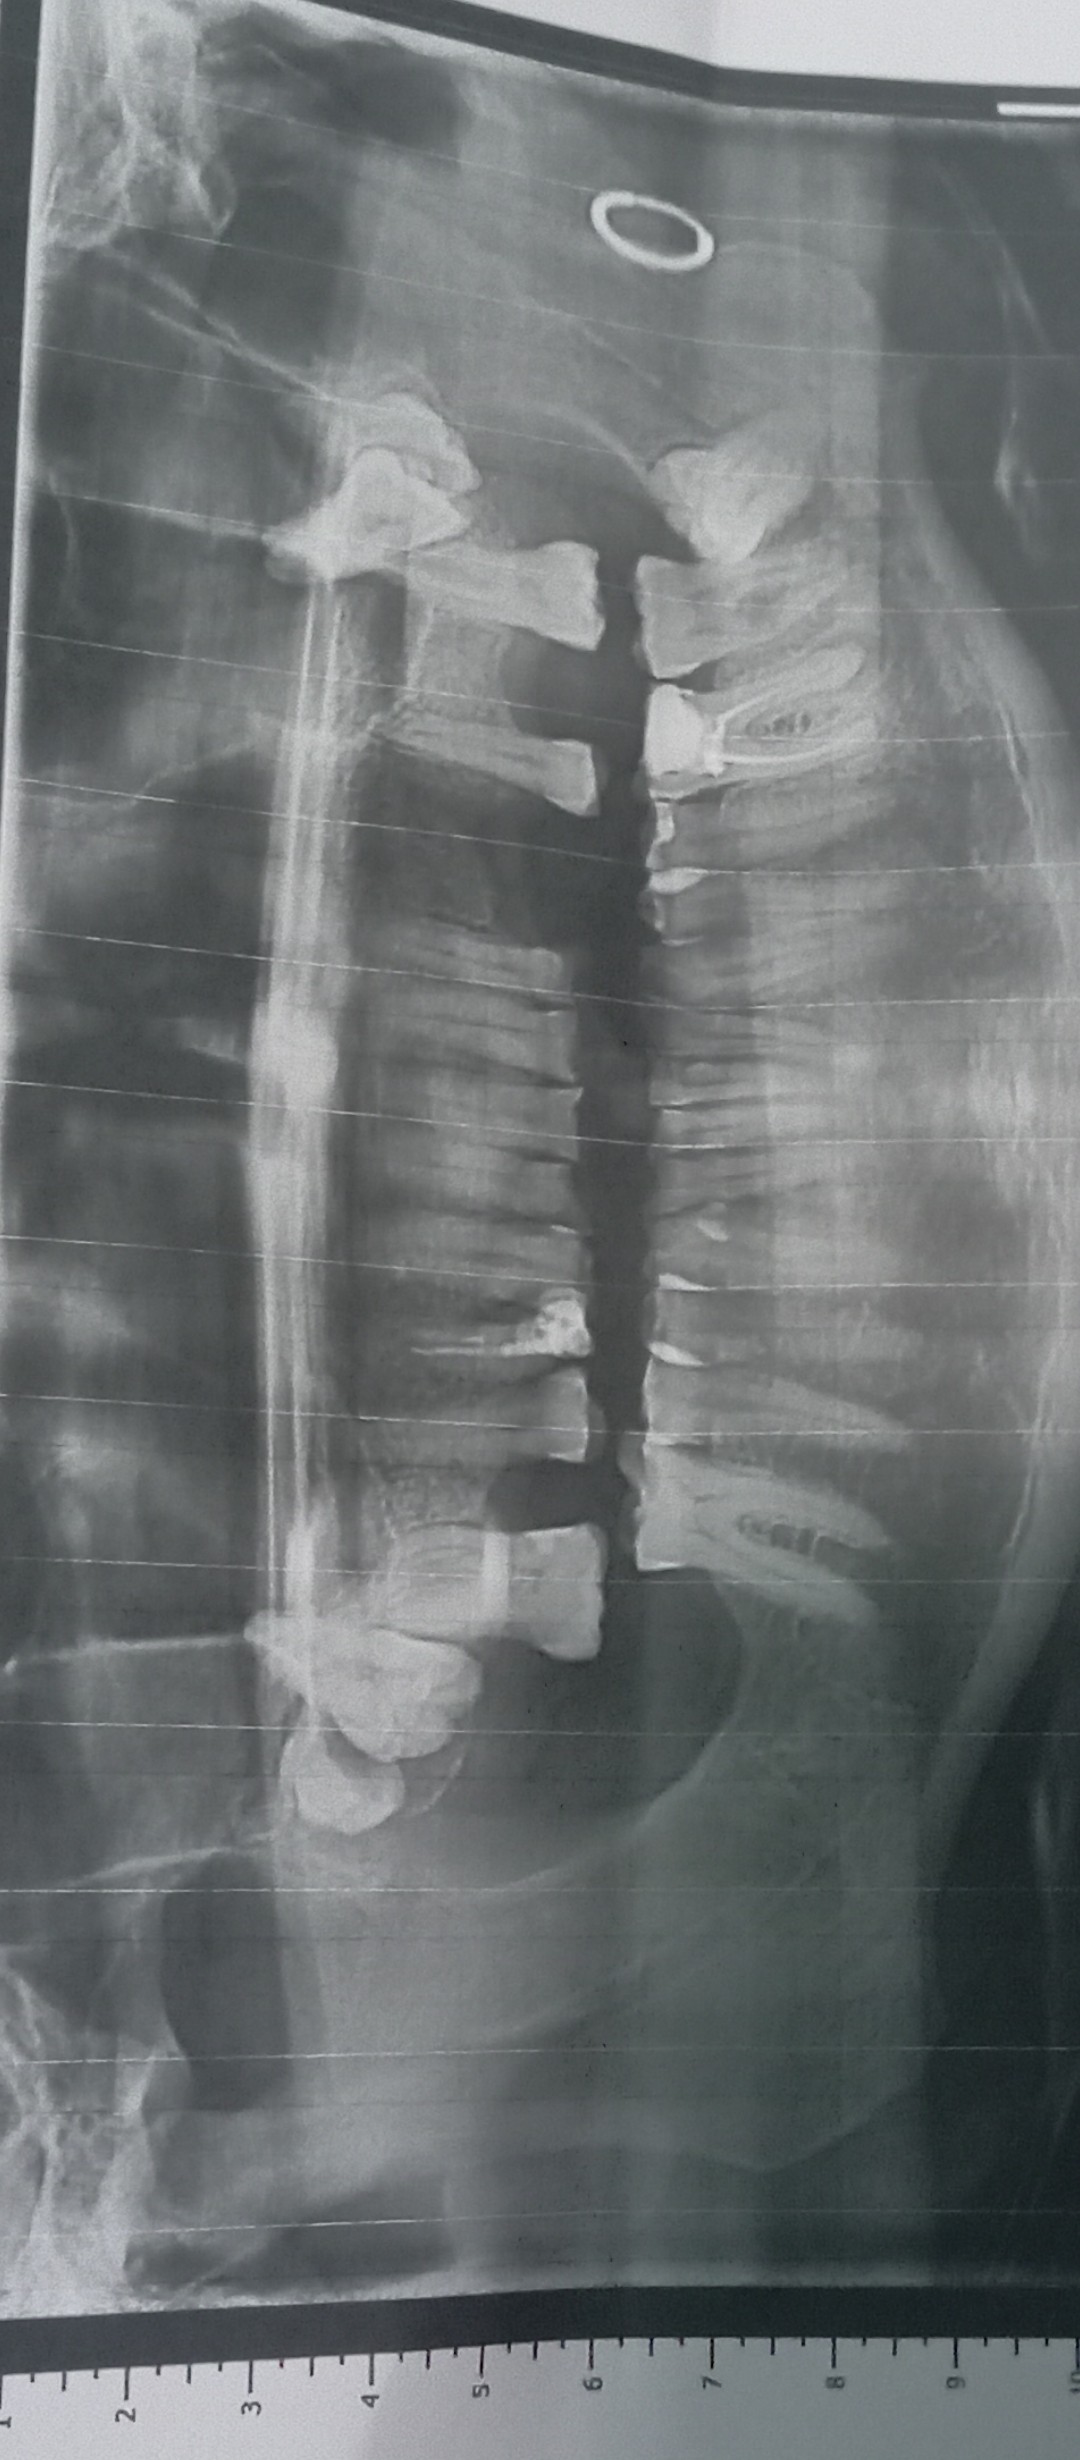

Вітаю, Добрый день. Неделю назад у меня начала болеть десна в нижнем ряду за седьмым зубом. Там как бы ранка Толи трещина и подпухло немного. Та восьмерка следит крепко. Мне 46 доктор говорил шо она уже не выйдет. Так вот через пару дней добавилась боль в шестом или седьмом зубе. Пульсирующая боль. Ночью не спал почти. Утром сегодня поехал к хирургу он удалил шестой зуб так как он плохой на снимке. Теперь я думаю решил ли я проблему, или это будет продолжаться и в е это из-за восьмёрки? Как думаете на снимке есть восполнение которое давало боль? Спасибо.